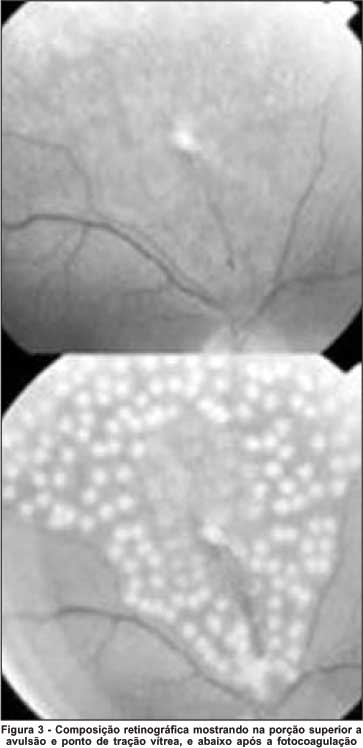

A análise identificou 13 olhos que obedeciam aos critérios propostos. Destes, 8 foram submetidos a fotocoagulação com laser de argônio verde e 5, a introflexão escleral com explante (esponja) localizado (Figuras 1, 2, 3, 4). Os principais aspectos examinados estão contidos na tabela 1. Do total, 6 casos eram do sexo masculino e 7, feminino. Idade oscilou entre 30 e 70 anos, média 53,6 anos.